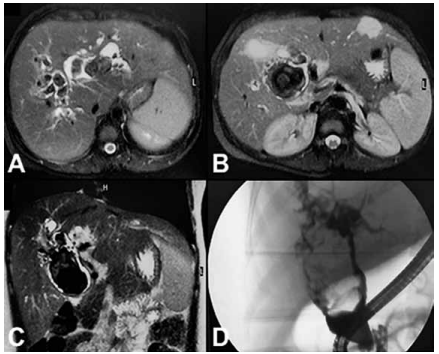

Paciente do sexo feminino, de 31 anos, apresenta dor em hipocôndrio direito, icterícia, colúria e acolia fecal há duas semanas. Exames laboratoriais mostram elevação de fosfatase alcalina, GGT e bilirrubina direta. A ressonância magnética

evidencia dilatação cística extensa da via biliar extra-hepática e intra-hepática, associada a múltiplas imagens sugestivas

de litíase intra-hepática. Foi realizada CPRE com colocação de próteses plásticas, sem melhora significativa dos níveis

de bilirrubina.

Exames de imagem apresentados a seguir: